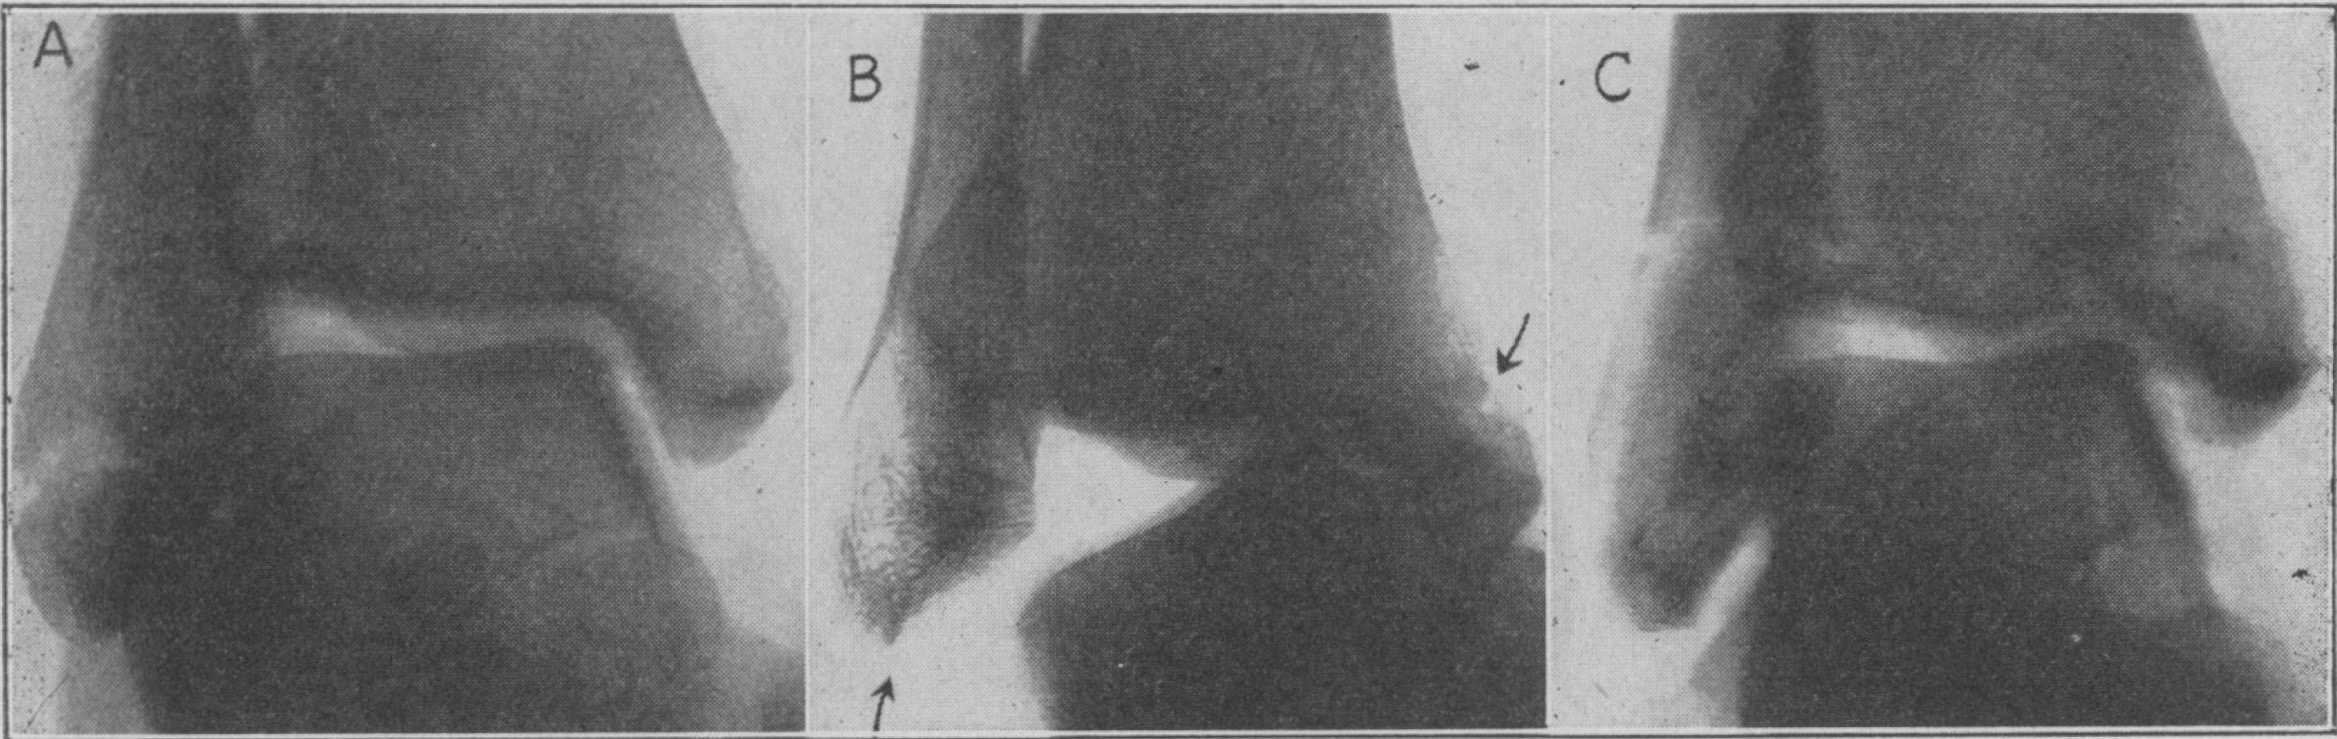

B, Supination-ADduction fracture, stage 2: detachment of the collateral lateral ligaments and fracture in the basis of the medial malleolus

C, Supination-ADduction fracture, stage 2: transverse fracture just proximal to the lateral malleolus (clinically a rare form of the fracture) and fracture in the basis of the medial malleolus. Lauge-Hansen 1950